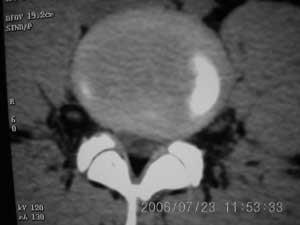

以下是引用xiaoniu在2006-7-23 12:47:00的发言:[br]椎体后缘软骨结节[br]【发病机制】尚未完全清楚,存在多种学说。一般认为青少年时期,脊柱负重压力及髓核膨胀性压力下,椎间盘组织通过椎体薄弱区疝入椎体内,局部骨小梁吸收被椎间盘组织代替形成软骨结节,周围骨小梁出现反应性硬化,逐渐形成骨壳包绕软骨结节。 椎体后缘软骨结节是椎间盘组织向后疝入椎体后缘的结果,为边缘性软骨结节的一种特殊类型。[br]【ct表现】椎体后缘类圆形、多囊状或不规则形的骨质缺损区,大小不一,位于椎体后缘正中或偏侧,其ct值等同于同层面的椎间盘,70~90hu,边界清楚,常有薄厚不一的硬化带。缺损区后方骨块突入椎管内,椎管狭窄,硬膜囊受压。[br]【鉴别诊断】本病诊断不难,需与以下疾病鉴别[br] 1 椎间盘突出钙化。2 后纵韧带骨化。3退变形成的骨赘。4锥体后缘撕裂性骨折。[br]上述疾病骨块影的形态及位置均各具特征,且椎体后缘均无低密度的骨结软节,鉴别不难。[br][br][本贴已被 xiaoniu 于 2006-7-23 12:52:32 修改过]